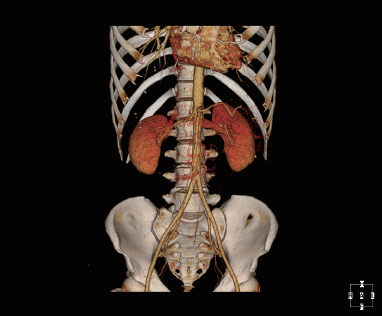

Умное рабочее место медицинского отображения

Согласно международному стандарту DICOM 3,0, само-разработанное рабочее место CIW совершенно исполняет с

стандарты медицинских изображений, включая функции получать, обрабатывающ, анализирующ, управляющ, помещающ в архив

запрашивающ, просматривающ, печатающ стандартный выход формата изображения, сочинительство отчета и так далее. В то же время, CIW также

содержит много других предварительных клинических применений.